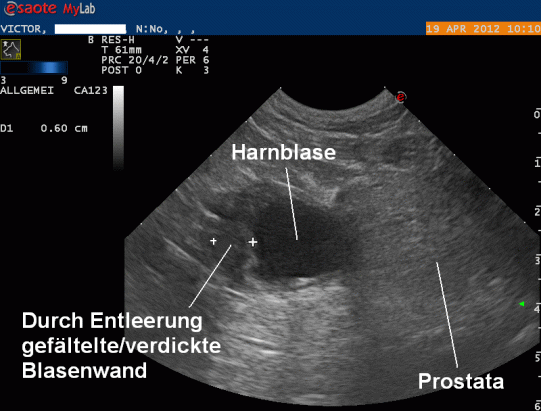

Nach dem Röntgen wird die Bauchhöhle per Ultraschall untersucht: Die Blase enthält nur wenig Urin; dadurch erscheint die Blasenschleimhaut im vorderen Blasenteil verdickt und aufgefältelt. Eine Geschwulst in diesem Bereich kann jedoch, obwohl von der Lokalisation her sehr unüblich, nicht komplett ausgeschlossen werden. Aus der Blase wir mit einer Kanüle Urin entnommen - die mikroskopische und bakteriologische Untersuchung zeigt, dass weder ein bakerieller Infekt, noch eine Entzündung in der Blase vorhanden ist.